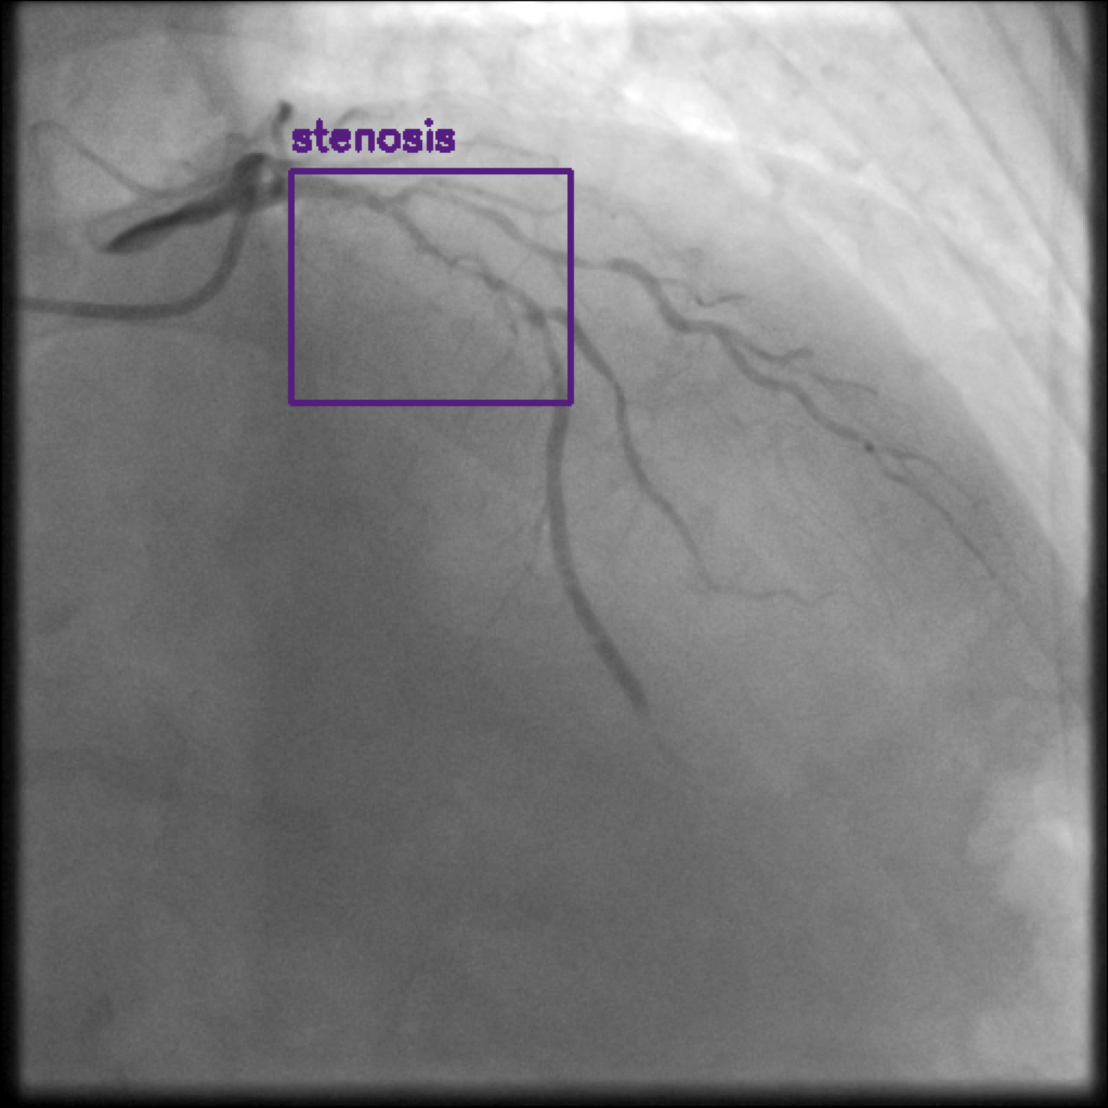

Figure 1 shows sample images from the ARCADE dataset with annotations for stenosis detection. The annotations highlight regions of arterial narrowing, providing ground truth data for training and evaluating object detection models.

To further assess the detection performance, qualitative results for three test images are presented in Figure 2. The first column shows the original images with ground truth annotations. The second, third, and fourth columns depict detections from DINO-DETR, Grounding DINO, and YOLO, respectively.

(a) Original (b) DINO-DETR (c) Grounding DINO (d) YOLO

The qualitative comparison in Figure 2 reinforces the trends observed in the quantitative evaluation. DINO-DETR produced fewer detections, occasionally missing relevant stenotic regions, consistent with its conservative detection strategy aimed at minimizing false positives [6]. Grounding DINO, although capable of identifying more regions, sometimes resulted in cluttered predictions due to over-detections [7]. YOLO provided a reasonable trade-off by effectively capturing anatomical structures while maintaining relatively high confidence scores and clear visualizations [5].